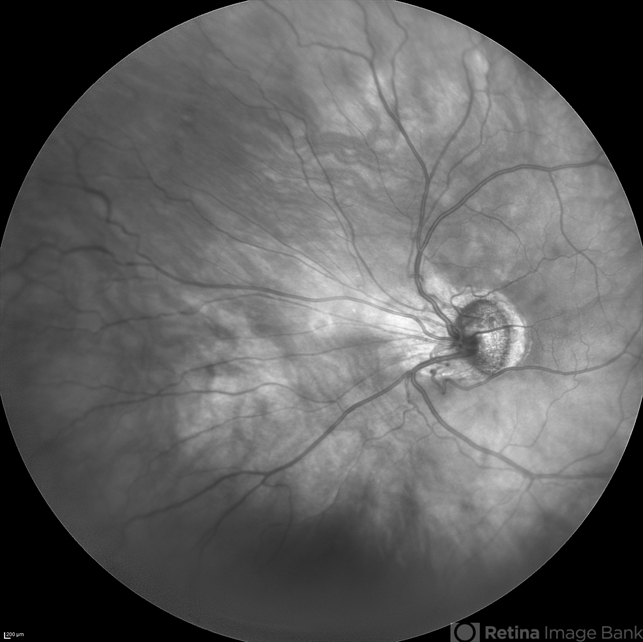

- rop, retinopathy of prematurity stage 3

Scanning laser ophthalmoscope

Spectralis, Heidelberg Engineering - Description

- IR cSLO widefield image of an 27-year-old man born as premature